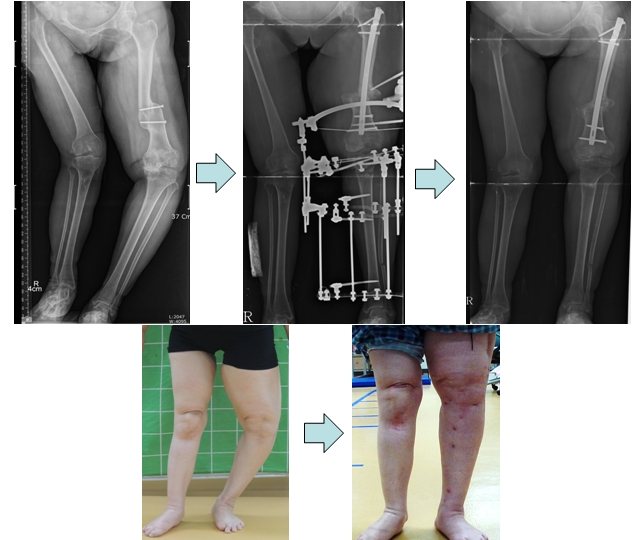

공지 왼쪽다리에 변형이 온 소아마비 환자의 하지 교정술관리자- 왼쪽다리에 변형이 온 소아마비 환자의 하지 교정술 Correction of left lower limb deformity in poliomyelitis.다음글공지 연골무형성증 환자의 키연장술 후 까치발 합병증 발..이전글공지 척추골단이형성증 환자의 고관절 교정목록